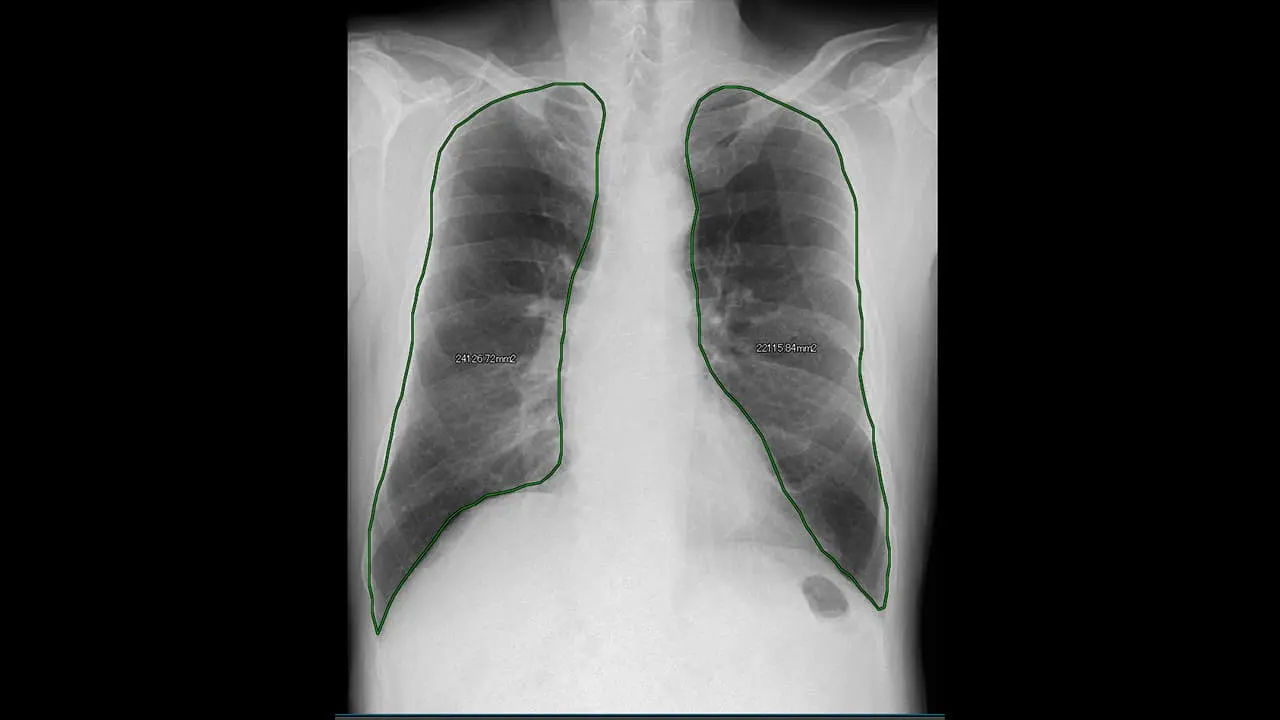

肺野面積経時変化グラフ

肺野内の血管影などを含む信号値パターンを追跡し、最大吸気位フレームを基準とした呼吸に伴う各領域の移動量をベクトル表示

肺野内の⾎管影などを含む信号値パターンを追跡し、呼吸に伴う各領域の移動量を計測することにより、動きの傾向をカラー表⽰